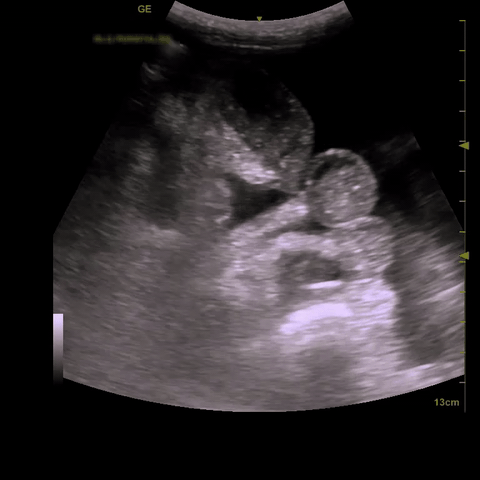

Intraluminal vs extraluminal free fluid: It is important to remember that there are numerous normal abdominal organs that are fluid filled e.g. blood vessels, stomach, gallbladder, and others that can become fluid filled in pathologic states such as small bowel or large bowel in the setting of obstruction. Especially if you are contemplating drainage you need to be certain you are draining abdominal free fluid. As a rule of thumb if fluid forms “corners” and sharp angles, settling into crevices, it is more likely EXTRAluminal and free flowing; see image on the left. If it has round borders it is most likely INTRAluminal or otherwise contained; see the image below on the right, that’s not ascites its a collection that was contiguous with bowel.

Complicated ascites: Though most of the abdominal free fluid encountered in IM is due to ascites from portal hypertension, exudative causes such as inflammatory, traumatic, and infectious collections that are non-gravity dependent or isolated to one part of the abdomen are also possible. Therefore it is important to not only look for abdominal fluid but also note its appearance as well. Notice in the images below the webbed and hazy appearance of the fluid; this patient had frankly purulent ascites requiring multiple abdominal drains.